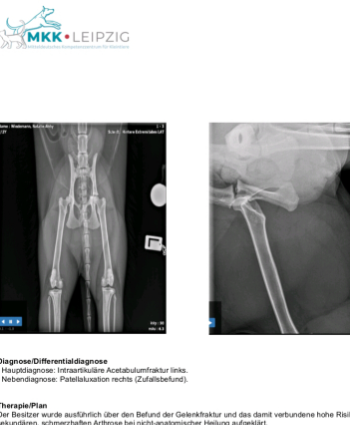

mit schwerem Herzen wende ich mich an euch, um Hilfe für meine geliebte Katze zu bitten. Sie hat sich einen komplizierten Beckenbodenbruch zugezogen und benötigt dringend eine Operation, bei der eine Schiene eingesetzt wird. Die Kosten für diese notwendige Behandlung belaufen sich auf 6000 €. Es ist kaum zu glauben, dass sie mit nicht einmal 3 Jahren schon so eine schwere Verletzung hat.

Wir haben bereits unser Bestes getan und waren in einer Notfallklinik sowie bei zwei Tierärzten, wobei allein die Diagnostik schon 650 € verschlungen hat. Ohne die Operation wird sie jedoch nicht mehr richtig laufen können und dauerhaft Schmerzen haben. Da wir finanziell leider sehr eingeschränkt sind, können wir die hohen Kosten nicht alleine tragen.